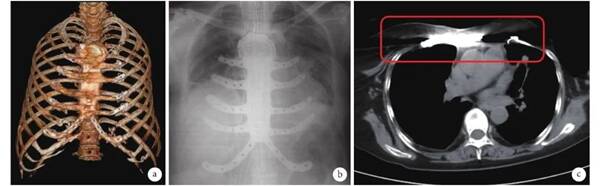

13 例患者均行胸壁病變擴(kuò)大切除術(shù)及 3D 打印鈦合金胸肋骨重建術(shù),其中 5 例患者術(shù)后發(fā)現(xiàn)腫瘤與肺葉粘連而行肺葉楔形切除,2 例行肌皮瓣轉(zhuǎn)移(采用背闊肌和胸大肌肌皮瓣)。所有患者術(shù)后均能維持胸壁完整性,未發(fā)現(xiàn)反常呼吸現(xiàn)象。術(shù)后通過(guò)復(fù)查 64 排胸部增強(qiáng) CT 掃描,并進(jìn)行三維重建可見(jiàn) 3D 打印鈦合金植入物與胸肋骨共同組成完整的胸壁結(jié)構(gòu),達(dá)到了個(gè)性化及解剖學(xué)的修復(fù)目的(圖3a)。在圍手術(shù)期內(nèi),2 例發(fā)生肺炎,但經(jīng)抗感染及對(duì)癥治療后均好轉(zhuǎn)。在術(shù)后 1 年隨訪中,13 例患者未發(fā)生植入物斷裂、移位、排斥、過(guò)敏等現(xiàn)象。1 例患者于術(shù)后化療 2 個(gè)月后已愈合傷口皮膚出現(xiàn)壞死致胸肋骨植入物裸露,后再次行手術(shù)取出植入物,并行背闊肌皮瓣轉(zhuǎn)移手術(shù)后傷口愈合。

3 3D 打印胸肋骨胸壁重建手術(shù)后

a:胸廓三維重建;b:X 線正位片;c:胸部 CT

2.3   影像學(xué)特點(diǎn)

X 線片上,因?yàn)殁伜辖鹬踩胛锩芏雀卟⑶疫h(yuǎn)大于皮質(zhì)骨,因此可顯示為清晰的金屬影,能很好地判斷植入物在體內(nèi)的形態(tài)和位置(圖3b)。在 CT 影像中,骨組織的 CT 值為 836 Hu,鈦合金植入物的 CT 值為 3 071 Hu,因此 3D 打印鈦合金植入物顯示為高密度的金屬影,且在所有患者的術(shù)后復(fù)查 CT 中,均可看到 3D 打印鈦合金胸肋骨植入物的影像學(xué)偽影,其偽影遮住了覆蓋的組織結(jié)構(gòu),從而對(duì)植入物周?chē)M織結(jié)構(gòu)的判讀造成不便(圖3c)。